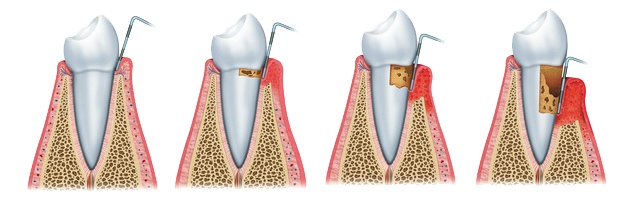

In fact, periodontal disease is a bacterial infection of the periodontium. Microbes in the dental plaque can attack the gums, bone, and can cause the loss of the affected tooth.

Periodontal disease needs more time to develop, and the negative effects are not negligible.